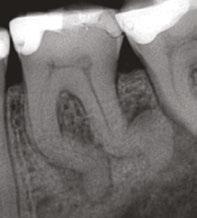

A 10-year-old female patient with a history of swelling and pain associated with tooth No. 20 was referred to our office. The patient exhibited severe dental anxiety. Upon clinical evaluation, a dens evaginatus was noted on the occlusal surface of the tooth (Figure 1). The tooth was sensitive to percussion, palpation, and bite stick while cold testing yielded no response. A periapical radiograph and CBCT scan (Carestream 9600) revealed a wide open apex and evidence of apical periodontitis, leading to the

Figure 1 (left): Dens evaginatus noted on the occlusal surface. Figure 2 (right): Preoperative periapical radiograph of tooth No. 20 showing evidence of apical periodontitis and a wide open apex

diagnosis of a necrotic pulp and symptomatic apical periodontitis of tooth No. 20 (Figures 2 and 3).